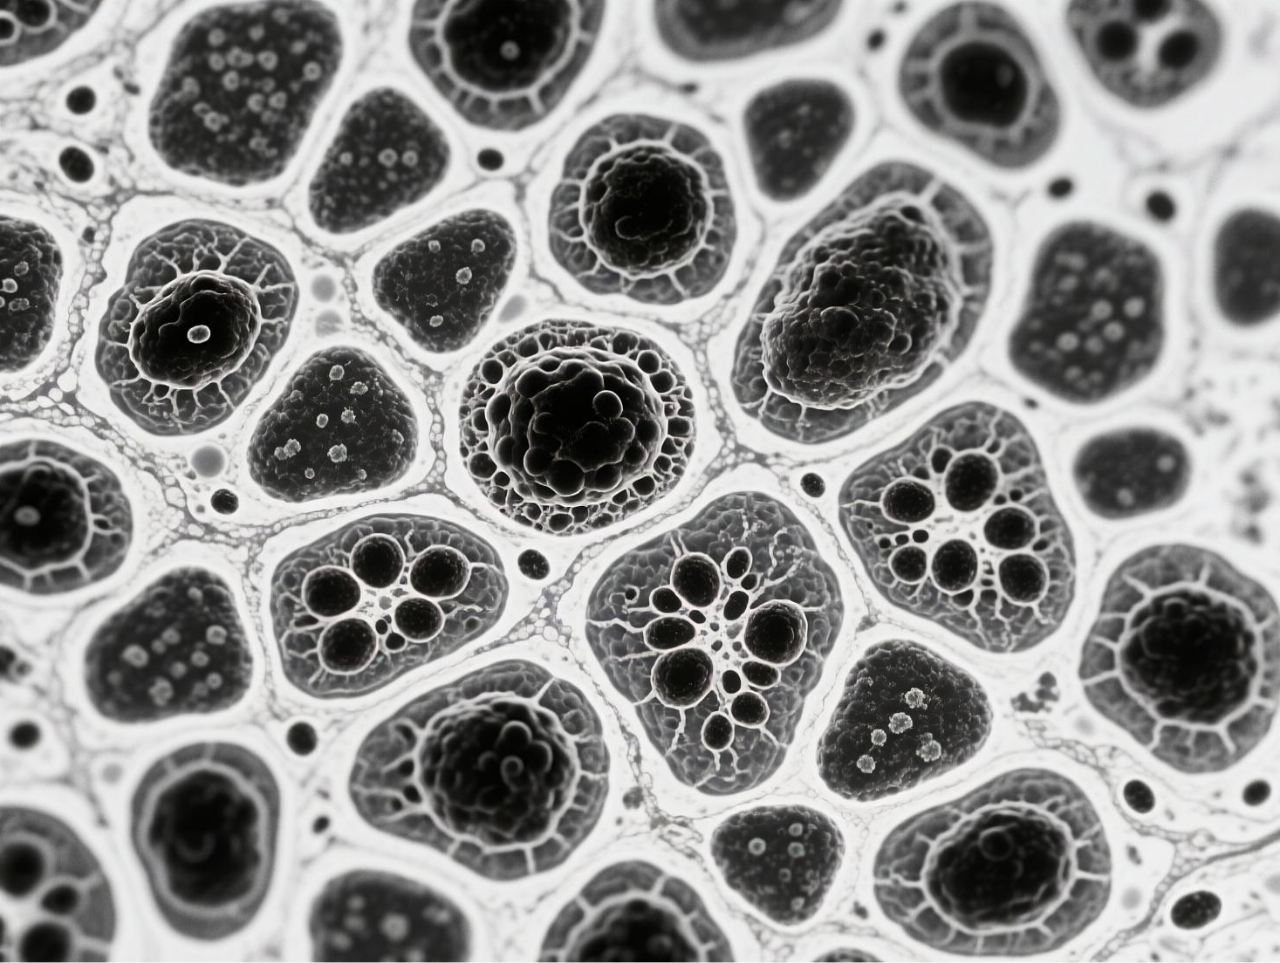

台式扫描电镜在本研究中发挥了关键的表征作用,为微气泡系统的结构验证提供了直观而精确的证据。研究团队使用188博金宝网页官网ZEM18台式扫描电镜对冻干后的BCG-MBs进行金溅射镀膜处理后,在不同放大倍数下观察其表面形态,清晰地展示了微气泡规则的球形结构以及BCG在微气泡表面的不规则分布状态。这一表征不仅确认了微气泡制备工艺的成功,还直观揭示了BCG在微气泡中的物理分布特征,为理解药物释放机制提供了结构基础。扫描电镜图像作为重要的形态学证据,有力支持了后续对微气泡浮力特性、药物释放行为及生物效应的分析,是连接材料设计与功能验证的关键环节。